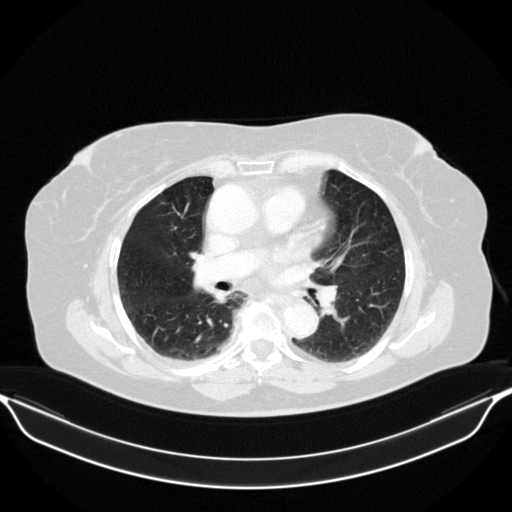

Reconstructed NATIVE CT scan (cycle consistency)

Full window (WL 1023.5, WW 4095 β†’ Low βˆ’1024, High +3071)

Actual HU range: [-1024.0, 1512.0]

Lung window (WL -600, WW 1500 β†’ Low βˆ’1350, High +150)

Actual HU range: [-1126.0, 150.0]

Mediastinum window (WL 40, WW 400 β†’ Low βˆ’160, High +240)

Actual HU range: [-160.0, 240.0]